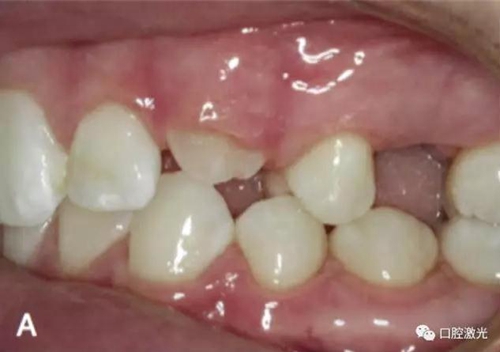

治療前

激光牙齦切割后即刻

在近似理想位置粘接托槽

6周后效果